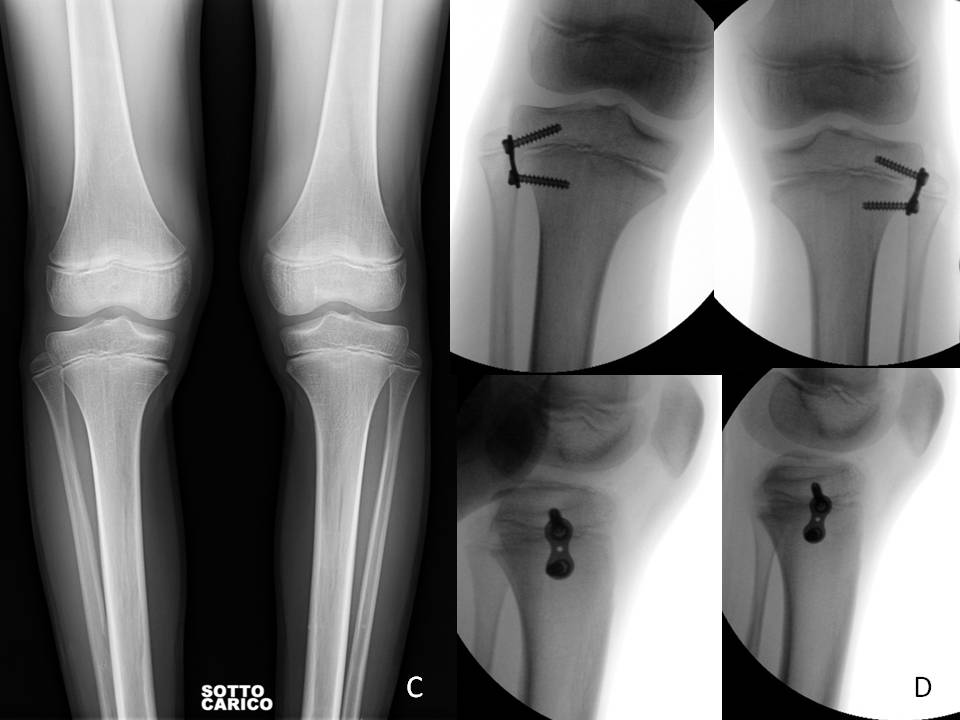

fig 5 C-D